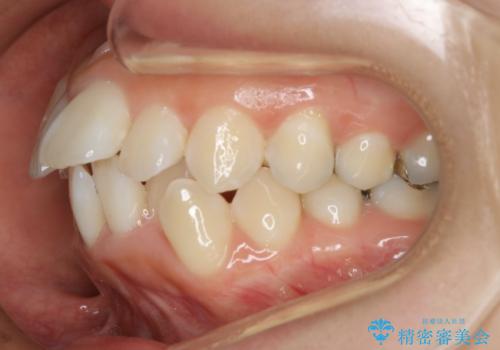

出っ歯が気になる 抜歯+ワイヤー矯正治療

- 歯のガタつきと出っ歯が気になるので矯正治療を希望し来院された患者様です。

上下顎とも歯を並べられるスペースが無く、口元を下げたいというご希望だったので、抜歯とワイヤー矯正を併用した治療を計画しました。

抜歯スペースを利用し口元を大きく下げることが出来ました。